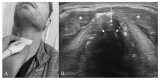

Airway management is a common and critical procedure in acute settings, such as the Emergency Department (ED) or Intensive Care Unit (ICU) of hospitals. Many of the traditional physical examination methods have limitations in airway assessment. Point-of-care ultrasound (POCUS) has emerged as a promising tool for airway management due to its familiarity, accessibility, safety, and non-invasive nature. It can assist physicians in identifying relevant anatomy of the upper airway with objective measurements of airway parameters, and it can guide airway interventions with dynamic real-time images. To date, ultrasound has been considered highly accurate for assessment of the difficult airway, confirmation of proper endotracheal intubation, prediction of post-extubation laryngeal edema, and preparation for cricothyrotomy by identifying the cricothyroid membrane. This review aims to provide a comprehensive overview of the key evidence on the use of ultrasound in airway management. Databases including PubMed and Embase were systematically searched. A search strategy using a combination of the term "ultrasound" combined with several search terms, i.e., "probe", "anatomy", "difficult airway", "endotracheal intubation", "laryngeal edema", and "cricothyrotomy" was performed. In conclusion, POCUS is a valuable tool with multiple applications ranging from pre- and post-intubation management. Clinicians should consider using POCUS in conjunction with traditional exam techniques to manage the airway more efficiently in the acute setting.